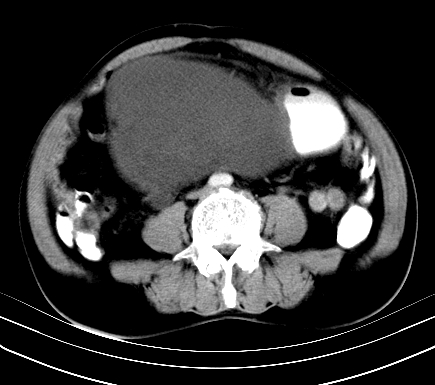

标题: CT19729B:男,74岁,因腿疼就诊,查体触腹部肿物,

增强扫描

动脉期

【ct表现】

1、肿块巨大,往往位于腹膜后,长大后才引起症状而就诊;那么位于腹膜后的肿瘤80%为恶性肿瘤。

2、实性肿瘤,增强扫描轻度不均强化,实性肿瘤一般不是好东西。

3、肿瘤边缘似见少许脂肪样密度。

4、腹膜后未见肿大淋巴结,但肿瘤于临近的肠管及组织接触紧密。

【诊断】

腹部占位,考虑位于腹膜后的恶性肿瘤,脂肪肉瘤(实体型)可能性大。

【分析】

1、腹膜后的肿瘤少见,但种类繁多,包括脂肪肉瘤、纤维组织细胞肉瘤、纤维肉瘤、平滑肌肉瘤、恶性畸胎瘤、神经肉瘤、神经母细胞瘤、血管肉瘤及横纹肌肉瘤等,其中脂肪肉瘤为较常见的一种肿瘤。

2、增强扫描强化不明显,除脂肪肉瘤以外,一般肿瘤强化中度以上。脂肪肉瘤可不强化或轻度强化。

术后病理结果:腹膜后脂肪肉瘤。